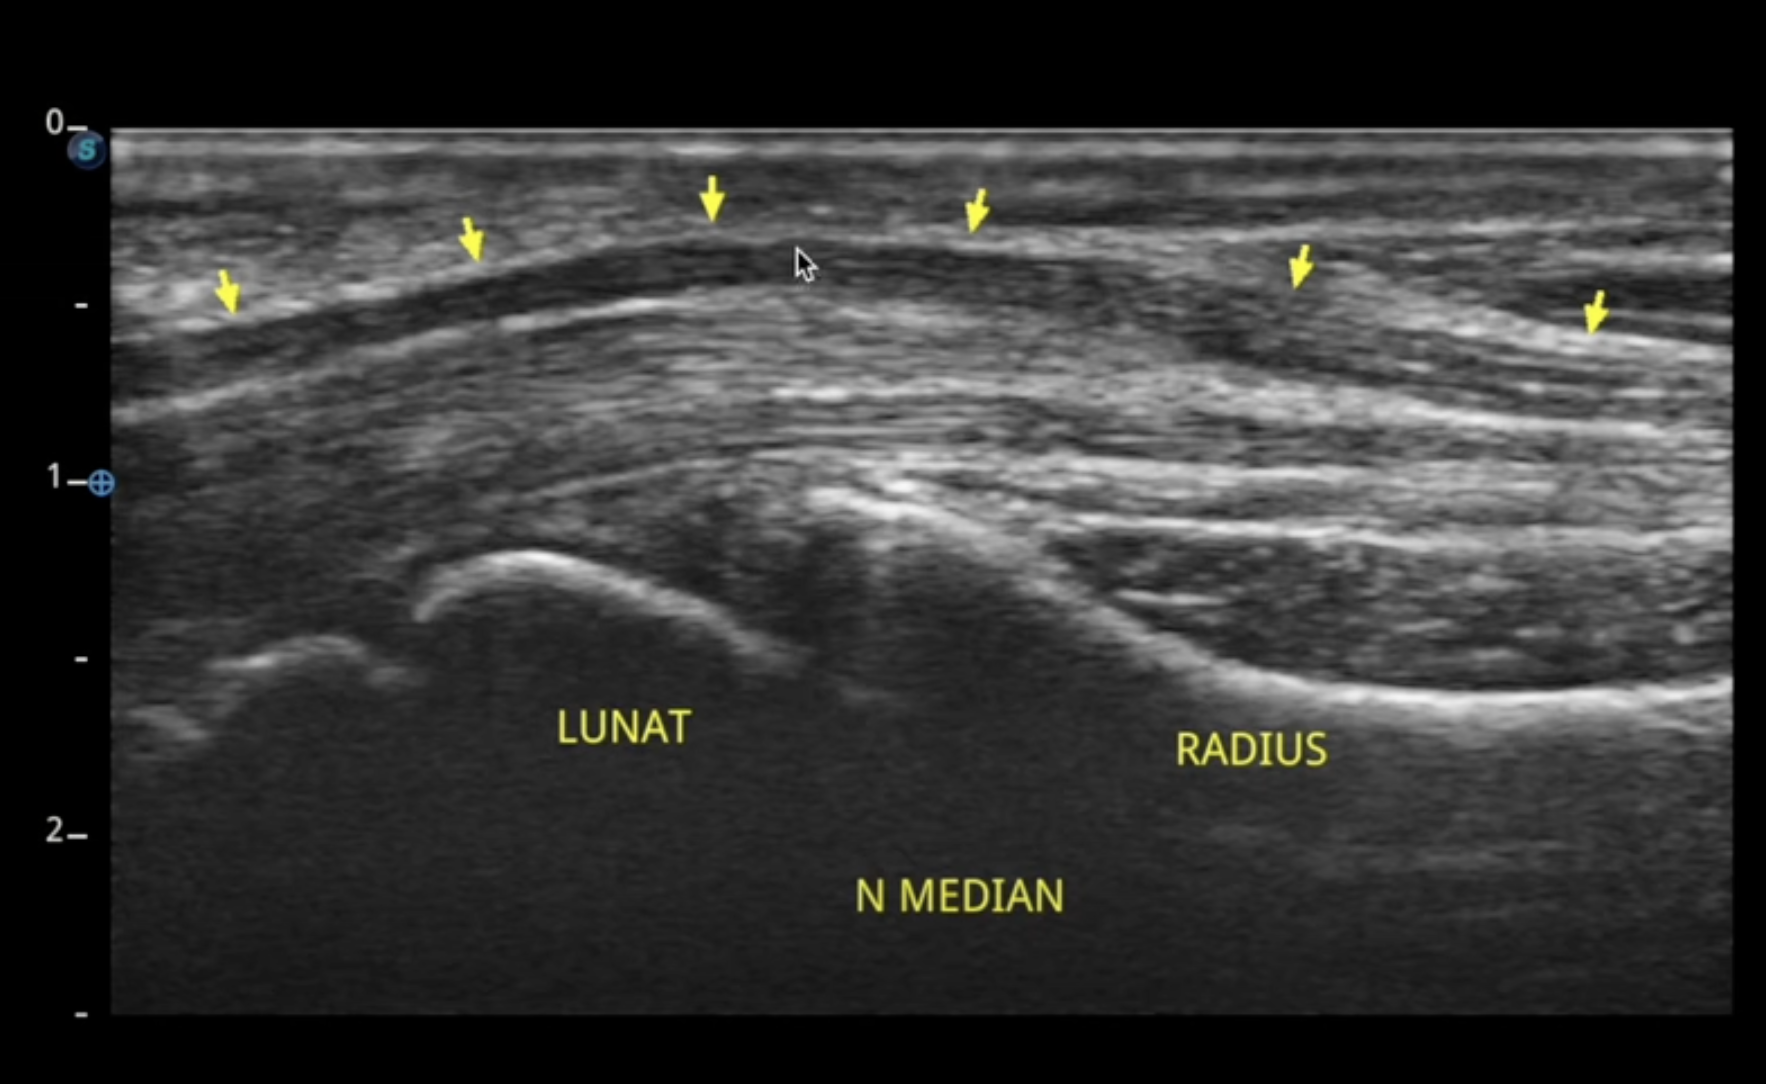

Au niveau du poignet, le nerf médian passe par le canal carpien accompagné par les tendons des muscles fléchisseurs des doigts.

Au niveau du poignet, le nerf médian est touché dans le syndrome du canal carpien en altérant la sensibilité de la main et la motricité des muscles de l'éminence thénar.